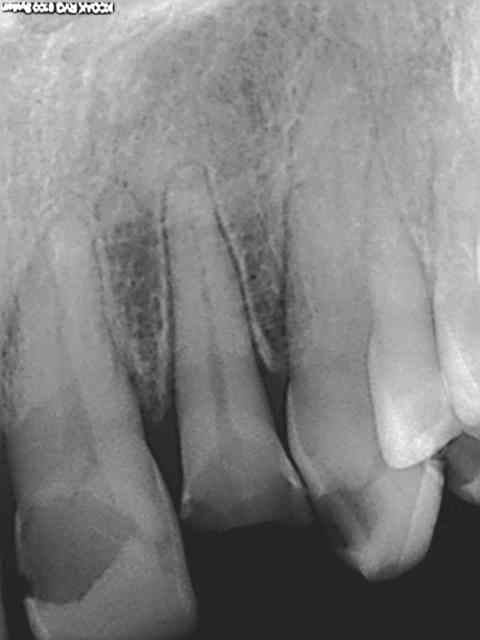

R1 jf6pzt - Eugenol

R2 k7cybs - Eugenol

R3 i3jjn6 - Eugenol

R4 dveqiy - Eugenol

Zoom incisives eb4rim - Eugenol

Retraitement et cour prov ej8sen - Eugenol

Canaux calcifi s e685ou - Eugenol

Avec provisoires o4ho8c - Eugenol

Lol ! je vois qu'on a la meme technique. c'est pas du no post no crown, mais je sais faire ca aussi. ))))))

Sur les monoradiculées, les tenons sont un peu trop courts. Avec les années, si l'os alvéolaire diminue, les risques de fractures de racines augmentent lorsque le bout du tenon se retrouve au niveau du rebord alvéolaire.

je fait extrêmement peu de tenon, mais tu nous présentes un travail soigné au moins d'un point de vue radiologique, sur la technique endo intrinsèque je laisse le soin a chacun de se faire une opinion